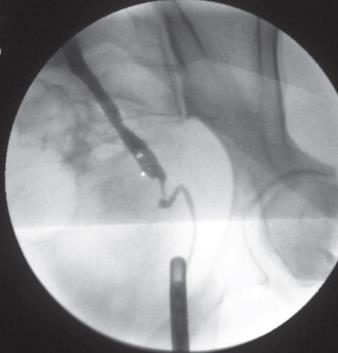

Pielografía retrógrada

Es una técnica radiográfica que permite demarcar, contrastar el uréter y el sistema colector renal (pelvis, infundíbulo y cálices) mediante la inyección de contraste radio opaco bajo presión en el uréter (8).

Técnica

Se trata de un procedimiento cistoscópico, que puede realizarse bajo anestesia local, requiriendo la misma preparación que una cistoscopía.

Paciente en posición litotomía, acceso endoscópico a vía urinaria inferior. Identificación de orificios ureterales. Una vez identificado el orificio a cateterizar, se debe utilizar algún tipo de catéter ureteral, sea de punta cónica, espiral o de oliva para la inyección directa de contraste en uréter. Se utilizan generalmente catéteres de 4 a 6 Fr.

Previo a la inyección de contraste se toma una placa simple y una vez asegurado la suave cateterización ureteral, no forzar para no dañar la submucosa y evitar una eventual perforación, se procede a la inyección de contraste. Debemos tener presente que la distancia entre el orificio ureteral y la pelvis renal varía entre 20 a 25 cm, por ello cualquier tipo de catéter que se utilice está demarcado. Se suele utilizar 10 ml de solución de contraste al 50%.